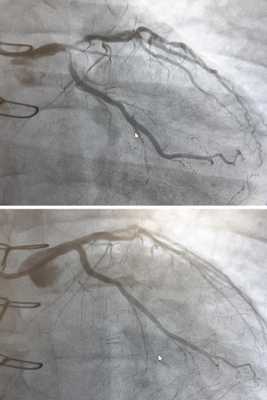

![Коронарография до и после стентирования]()

Коронарная ангиопластика и стентирование

Это современная технология восстановления проходимости коронарных артерий при ИБС. Смысл заключается в раздувании атеросклеротической бляшки специальным баллоном и укреплении сосудистой стенки металлическим каркасом - стентом. Коронарная ангиопластика проводится без разрезов у пациентов с тяжёлой стенокардией или инфарктом миокарда.